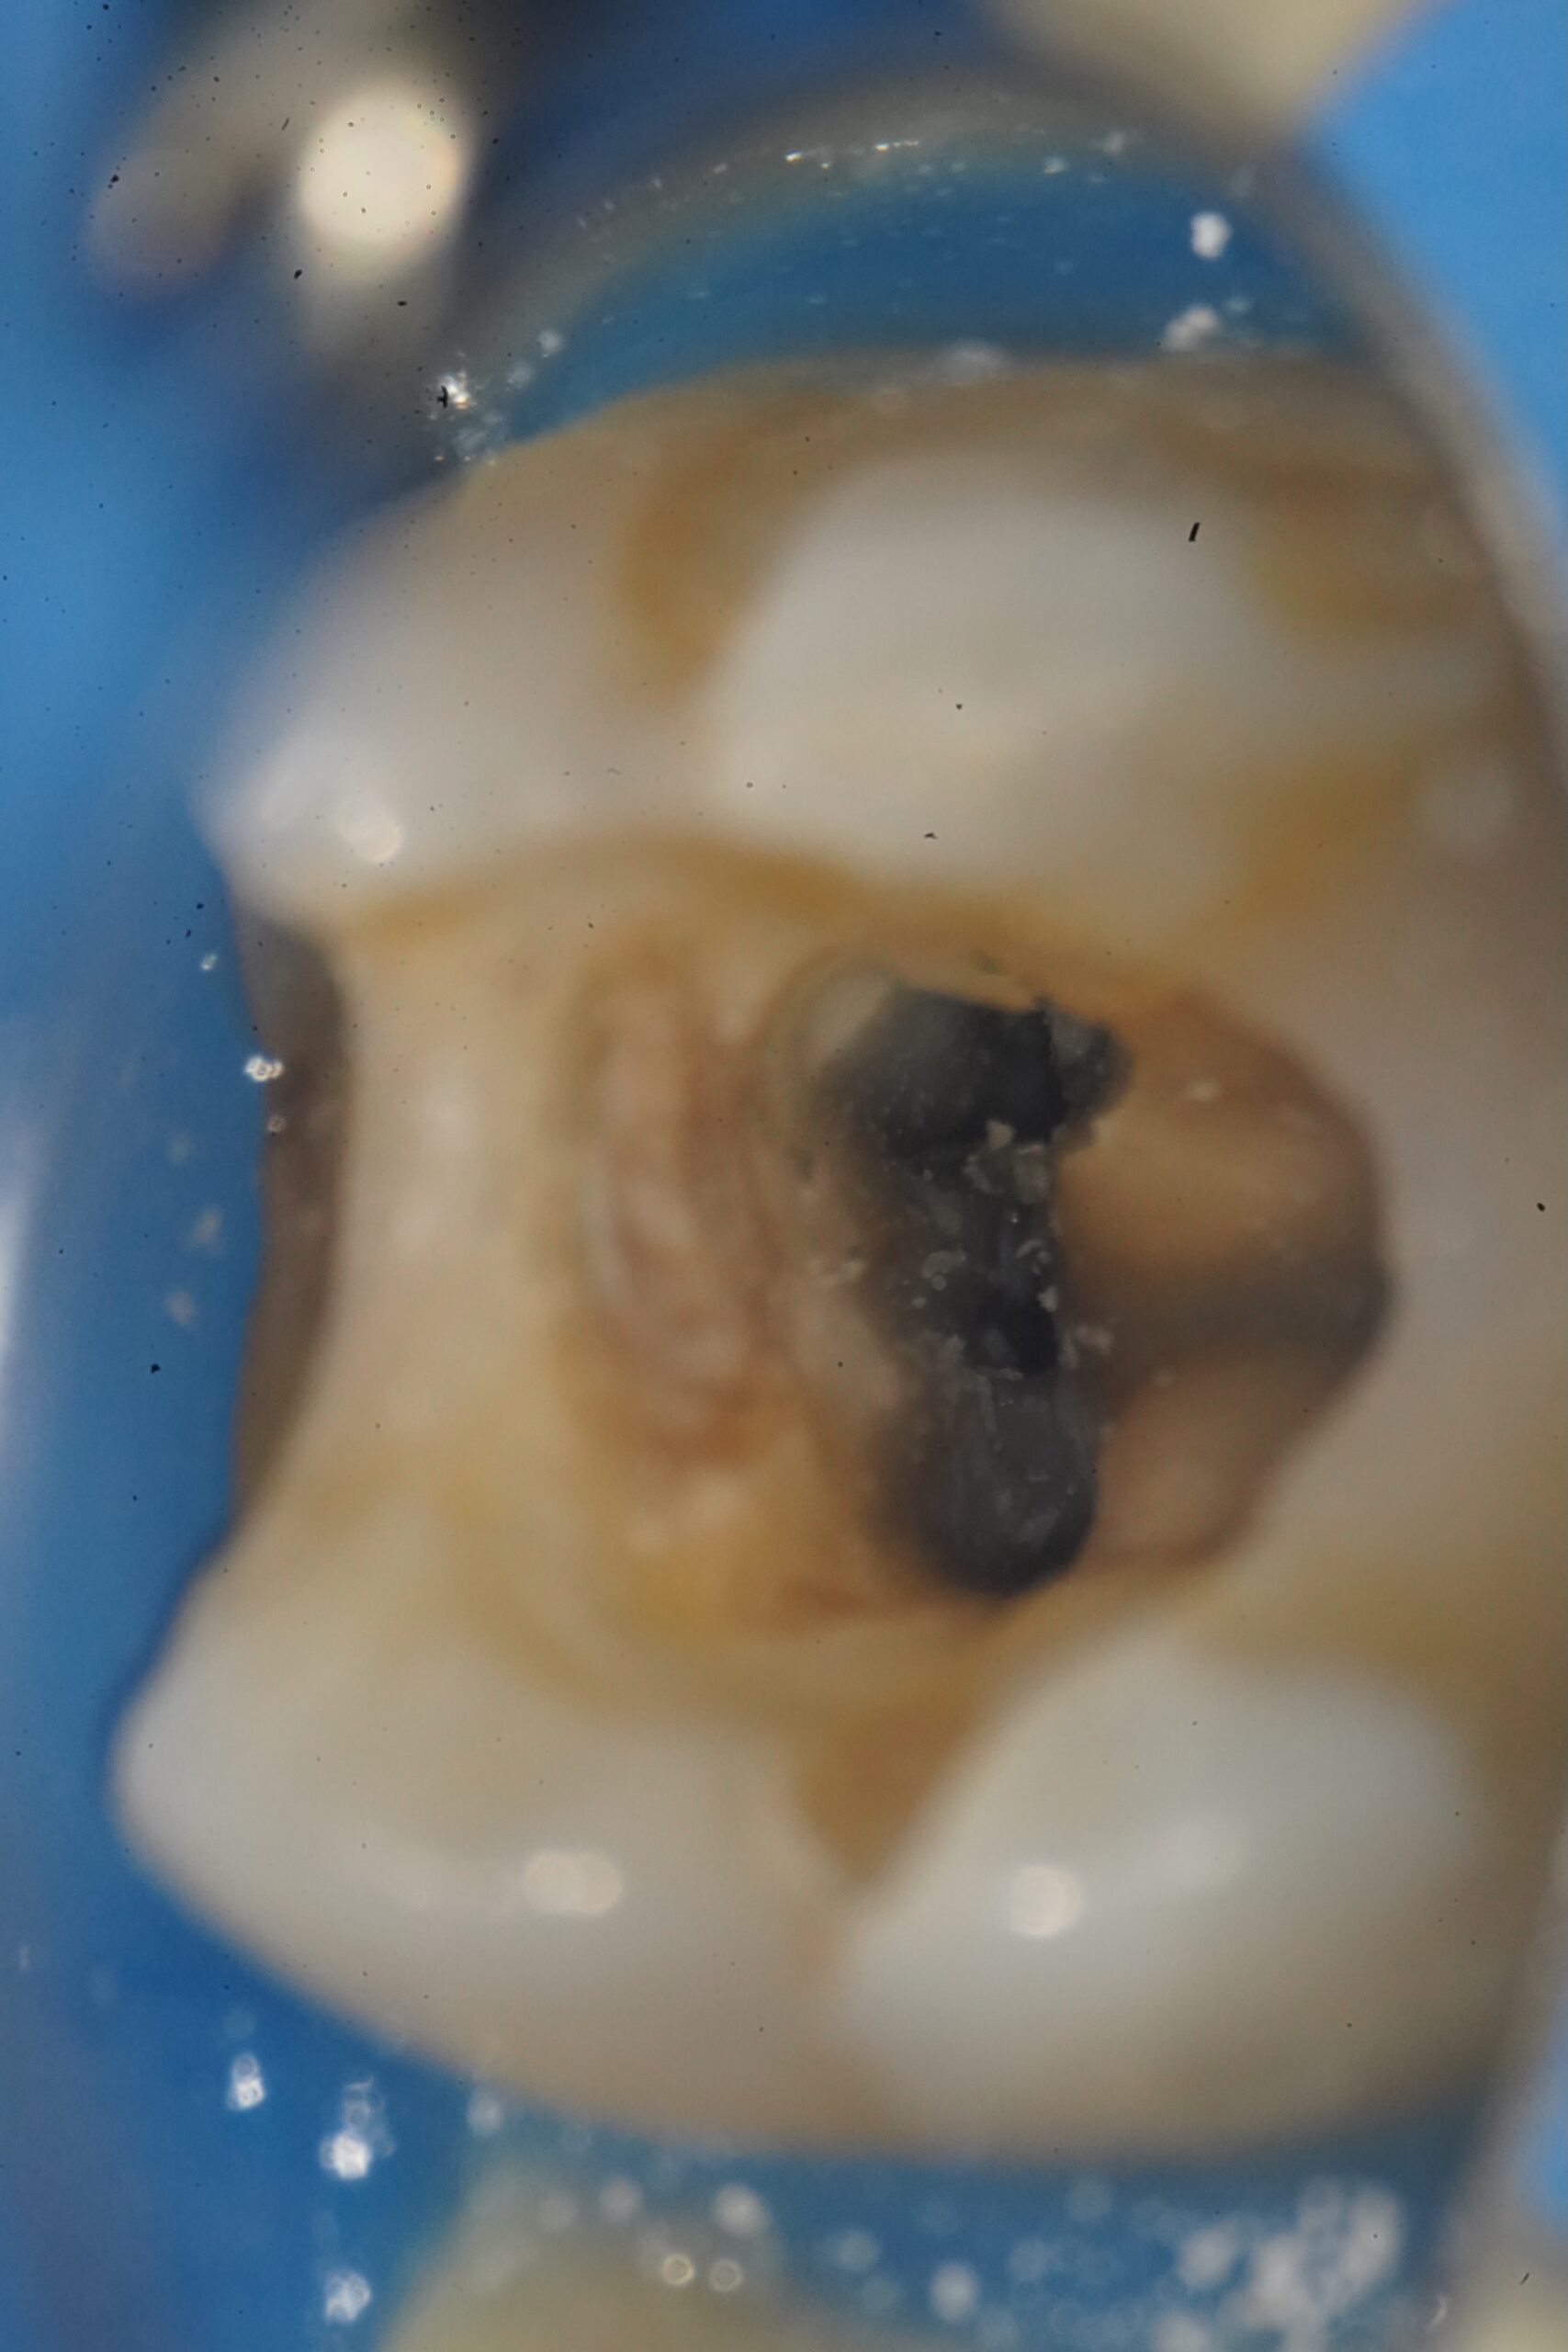

治療前

「他院で根管治療をしたが、中にファイルが残っていると言われた」——当院にもよく寄せられるご相談です。器具破折は拡大視野で丁寧に行っても稀に起こる根管治療の偶発症。重要なのは、感染の有無と位置を正確に評価し、歯を守れる選択を行うことです。

(CT+マイクロで診断)

感染所見:痛み・腫れ・瘻孔・X線/CTでの透過像

位置:頸部/中間/根尖1/3、直線化のしやすさ、湾曲の強さ

超音波+マイクロでの除去

顕微鏡下で視認し、超音波チップで振動・緩みを作って摘出。頸部〜中間サードで直線化できるケースに有効。